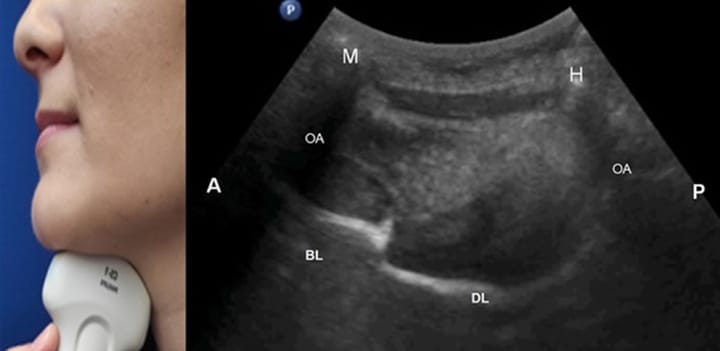

Échographie Échographie appliquée à la rééducation oro-maxillo-faciale : pourquoi tout kinésithérapeute maxillo-facial devrait avoir un échographe ?